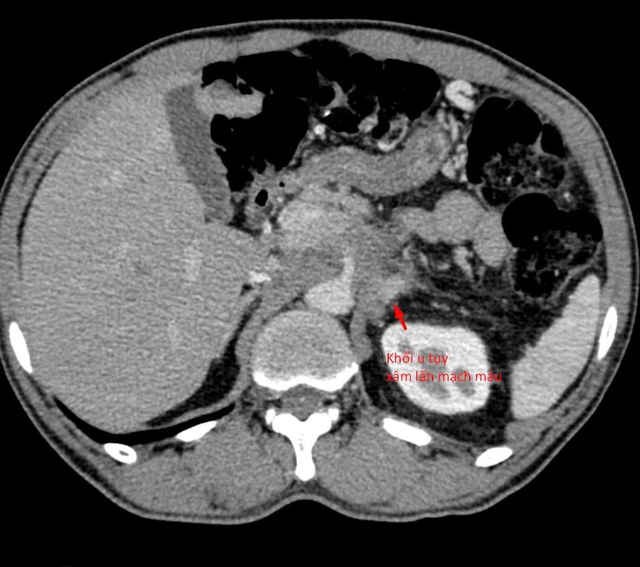

Khối u tủy xâm lấn mạch máu.

Sau khi tiếp nhận bệnh nhân, các bác sĩ đã tiến hành đánh giá lại toàn bộ cấu trúc giải phẫu và đường tiếp cận khối u. Hầu hết các hướng sinh thiết thông thường đều không khả thi do nguy cơ tổn thương mạch máu lớn và các tạng quan trọng.

“Chúng tôi chỉ còn một ‘khe cửa hẹp’ duy nhất: tiếp cận từ phía sau, xuyên qua khoảng giữa cột sống và thận. Đây là đường vào rất khó, rủi ro cao và đòi hỏi kỹ thuật can thiệp cực kỳ tinh vi”, bác sĩ Giang chia sẻ.

Dưới hướng dẫn của CT đa dãy độ phân giải cao, mũi kim sinh thiết được đưa chính xác qua khe an toàn duy nhất, tiếp cận khối u và lấy mẫu bệnh phẩm thành công. Thủ thuật diễn ra an toàn, không ghi nhận biến chứng, mẫu mô đạt yêu cầu để phục vụ chẩn đoán.